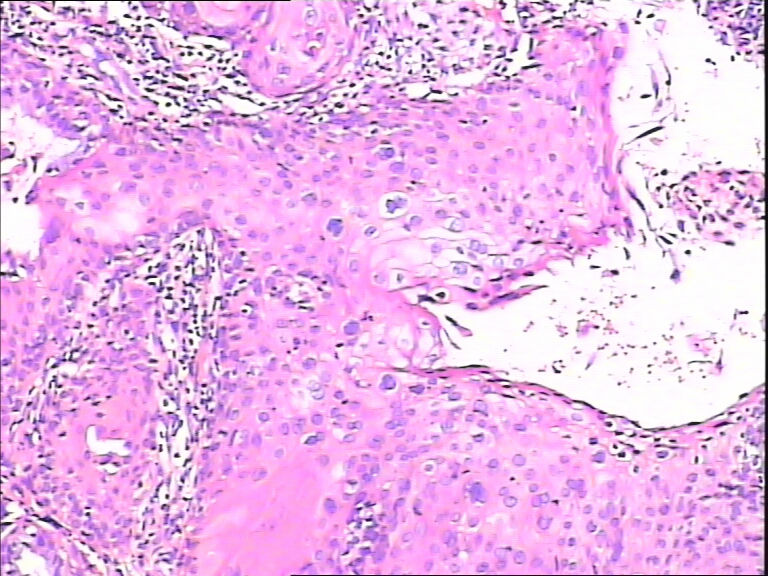

45y,触血,宫颈多点活检。